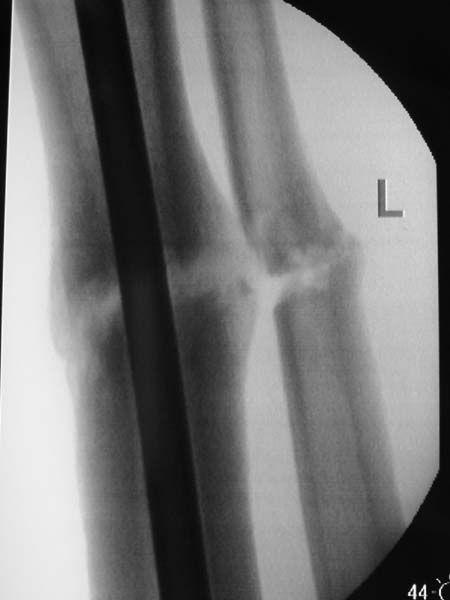

No hollow reamers and nails are still availble yet, so UTN 10 mm was used. After perQ osteotomy of the fibula i tried to open the canal, and the awl was passed to the distal fragment only after closed mobilization of the site to make some antecurvation. It resulted with some anterior translation of the distal fragment :( After impaction the nail was locked dynamically. Images attached. Comments/critics are welcome.

I believe this nailed nonunion of the tibia shaft will likely go on to uneventful healing. Good job.

Today the case was criticized at the week clinical report for the antecurvation deformity... Un our vice-director tries to prove that such a malalignment is of great clinical importance.

I would expect the deformity of the case of nailed tibia shaft nonunion (slight apex posterior and slight posterior translation) to be of no definite and small theoretical clinical importance.